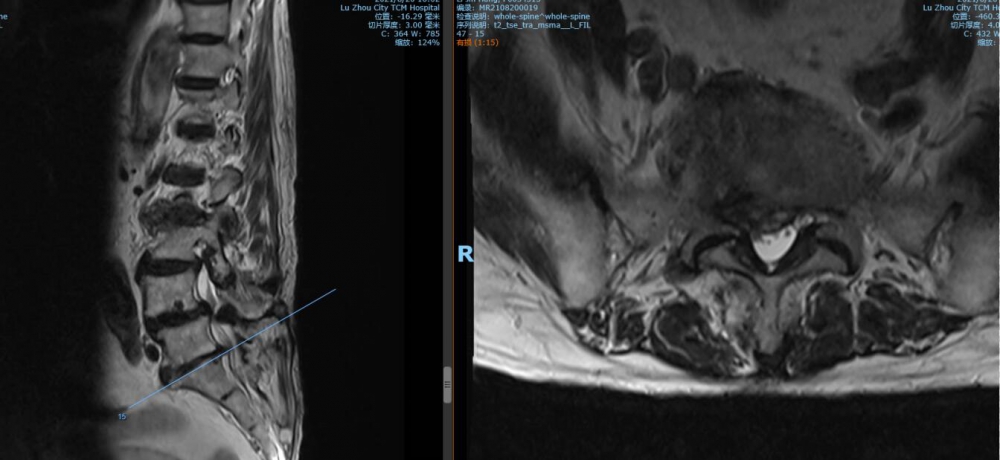

5 骶1椎間盤MRI